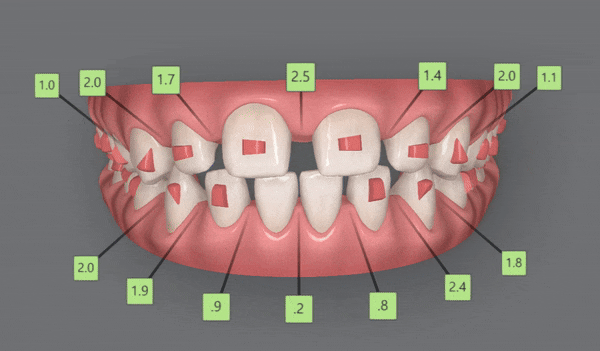

2nd Clincheck

치료기간 24/1~24/6

잠실인비절라인잘하는치과

유펜바른치과의 인비절라인라이트케이스의

두번째 클린체크인 추가 14개의 장치를 통해

인비절라인교정치료가 잘 마무리 되었습니다 :)

인비절라인 교정을 통해

앞니가 바르게 배열되면서

앞니의 외상을 줄여주고

치아사이의 공간을 닫을 뿐만 아니라

위, 아랫니의 교합관계도 개선이 되었습니다.